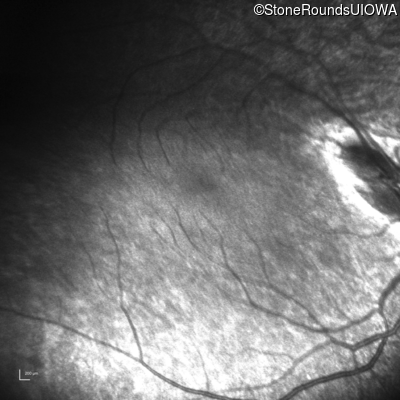

Infrared Fundus Photograph - Left - Light Perception

Exemplar